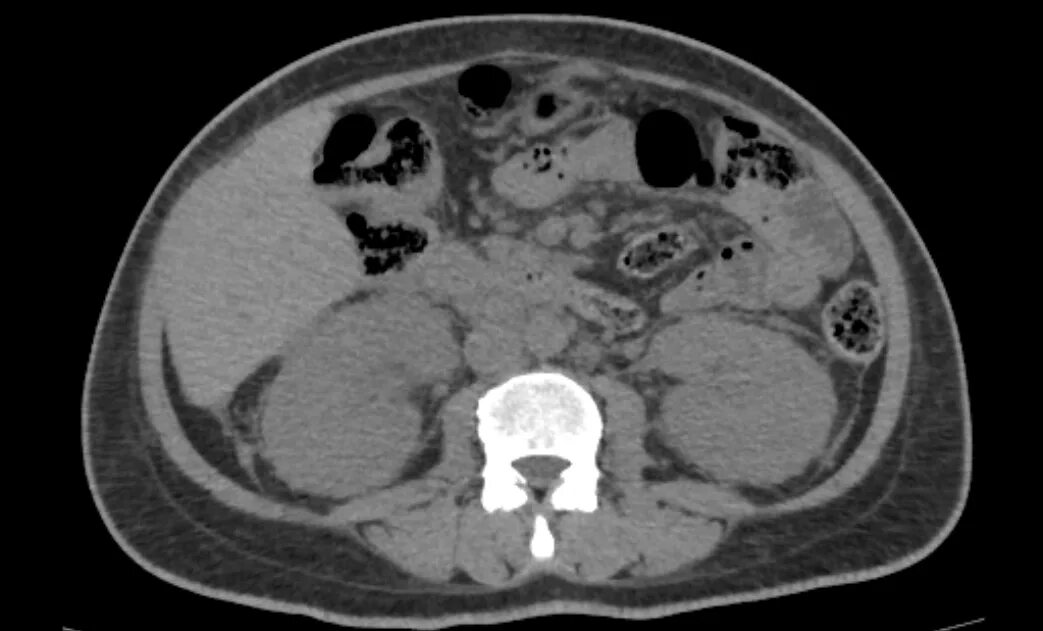

Пиелонефрит кт